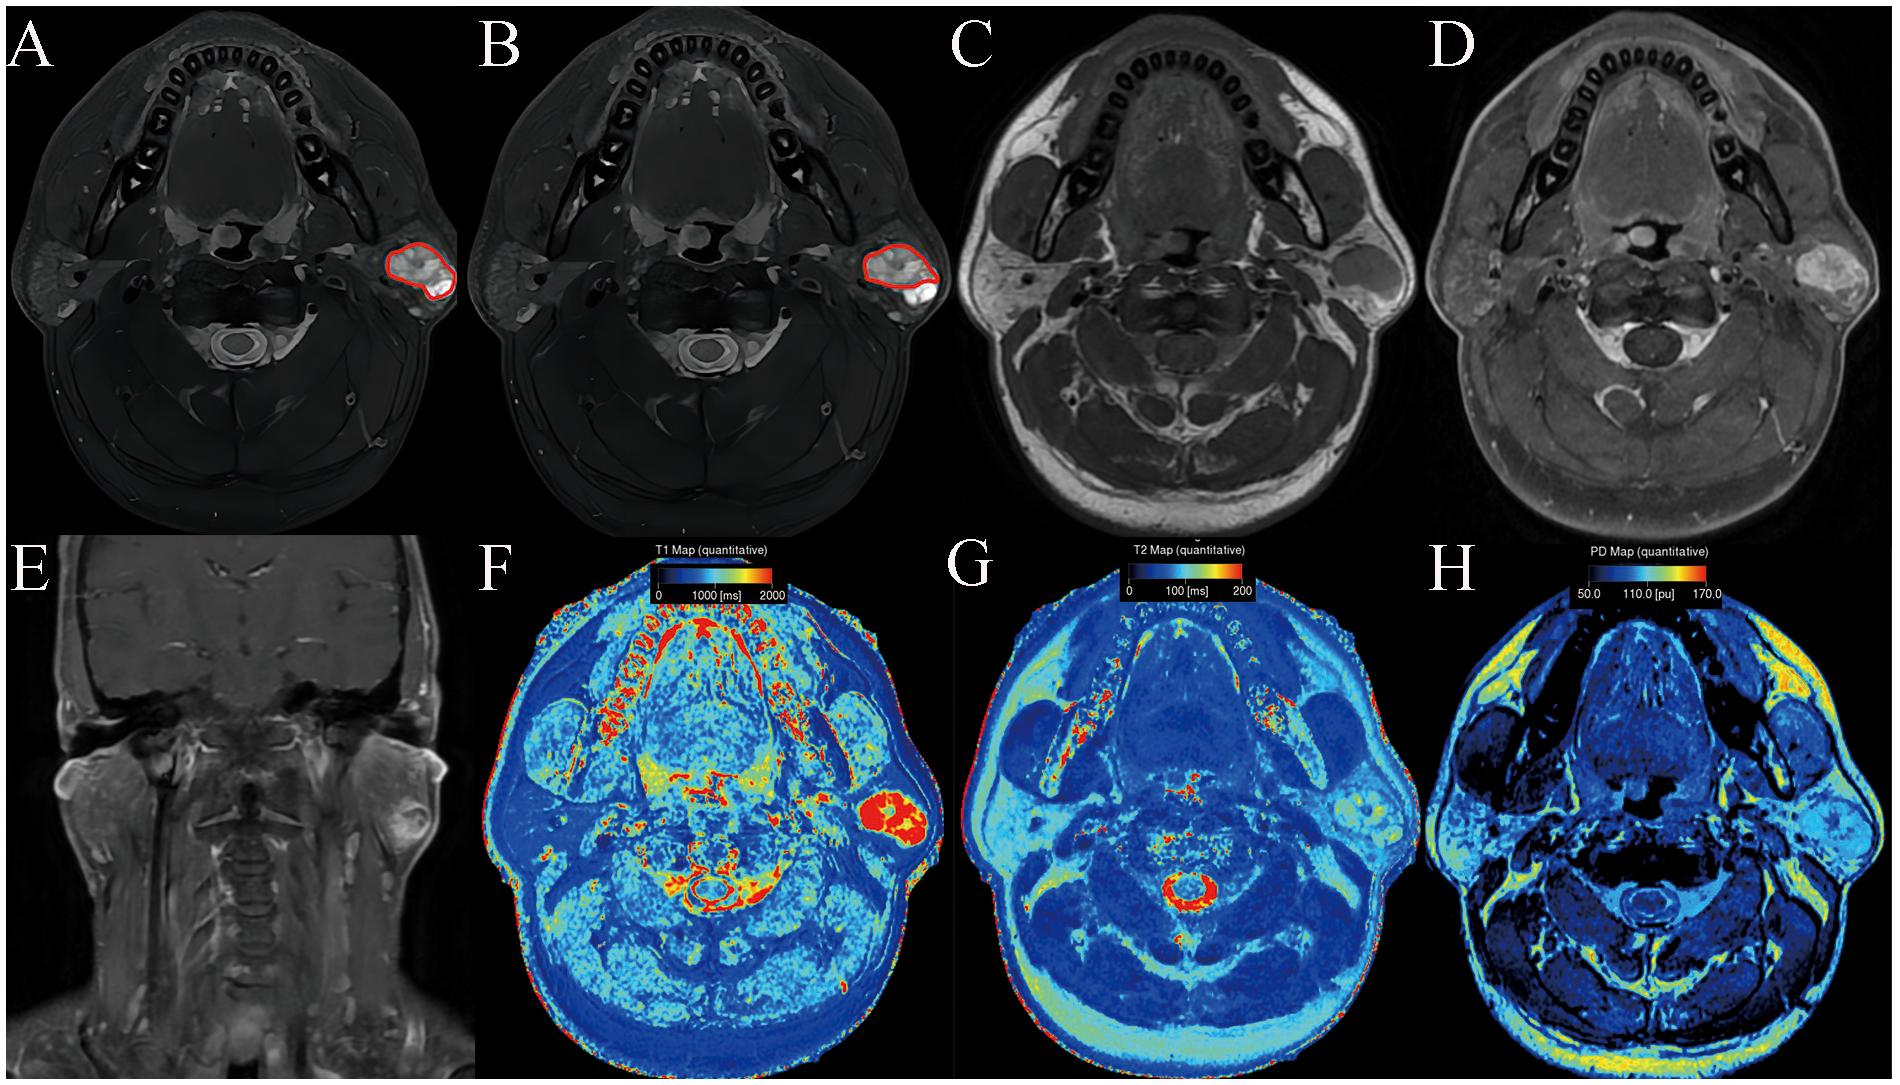

Table 3 summarizes SyMRI’s quantitative parameters for PA and WT. The T1, T1sd, T2, PD, T1ratio, T2ratio, and PDratio of PA derived from full-lesion ROI were significantly higher than those of WT (P < 0.05). The T1, T1sd, T2, T2sd, PD, PDsd, T1ratio, T2ratio, and PDratio of PA derived from partial-lesion ROI were significantly higher than those of WT (P < 0.05) (Figures 1, 2). In terms of T2sd and PDsd derived from full-lesion ROIs, there were no significant differences between PA and WT (P > 0.05). The T1, T2, and PD values measured on the masseter muscle did not differ significantly between the two types of lesions (P > 0.05).

Figure 2. Warthin’s tumor of the parotid gland in a 77-year-old male subject. The ROI delineation methods included the largest area of the largest section (full lesion, A) and the solid portion within the largest section (partial lesion, B). On conventional MRI, the solid component shows moderate signal and cyst/necrosis shows hyperintense on T2WI (A, B), a well-defined border (C), and moderate enhancement on contrast enhanced T1WI (D, E). In comparison with PA, it demonstrated significantly lower SyMRI-derived quantitative parameters for partial-lesion ROI (T1: 1723 ms; T1sd: 269 ms; T2: 79 ms; T2sd: 7 ms; PD: 86.4 pu; PDsd: 6.1 pu) on axial T1 mapping (F), T2 mapping (G), and PD mapping (H).